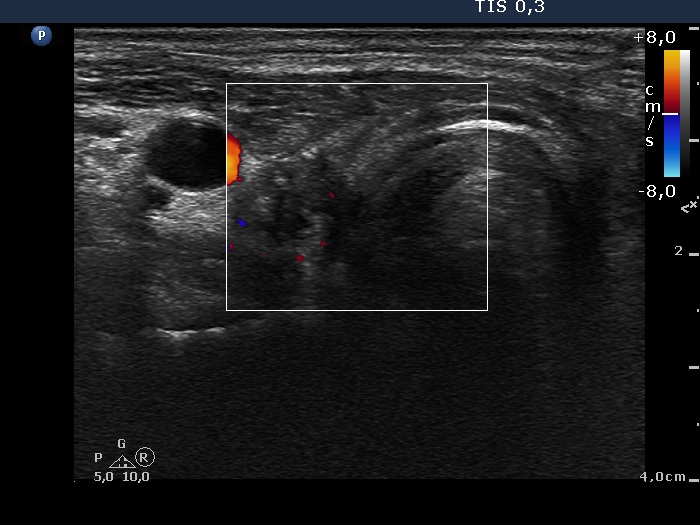

One month after surgery (second row of images):

Clinical data: The patient had no complaints.

Palpation: There was a relatively large, painless mass in the left thyroid bed.

Result of blood test: euthyroidism on daily 125 microgram levothyroxine (TSH 0.87 mIU/L).

Ultrasonography. The thyroid parenchyma was replaced by regenerative tissue. There was a cystic lesion in the left thyroid bed with a maximal diameter of 23 mm.